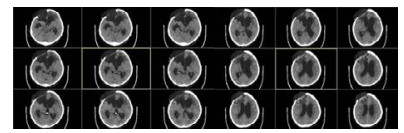

病例2,女,60岁,2017年10月以“动脉瘤夹闭和脑内血肿清除术后6个月,意识进行性下降2个月余“入院。入院时植物状态;查体:GCS 8分,双瞳孔3.0 mm,对光反应灵敏,双侧病理征阴性。右侧额颞部颅骨缺损大。入院头颅CT示脑室扩大。诊断为:右前交通动脉瘤术后、脑积水、头皮下积液、右额颅骨缺损、持续性植物状态(图 3)。

| 右侧额颞部颅骨缺损7 cm×9 cm,双侧脑室和三脑室扩大 图 3 2017年10月12日病例2的CT |

入院后于2017年10月30日行“颅骨修补+V-P分流术”。术后将分流管压力逐步调至0.5。患者术后意识无明显改善,复查CT示脑室仍显著扩大。观察2周后病情同前,遂将储液囊外接引流,每日引流量约200 mL,持续3 d,未见行为学及影像学明显变化。加大引流至每日300 mL,持续3 d后,患者自主睁眼增多;引流量增至每天400 mL左右,患者能呼唤下睁眼和视觉追踪。而停止脑脊液外引流后,患者则退步到引流前水平。决定通过按压储液囊促进脑脊液引流(按压600次/d),持续10 d后,睁眼时间延长但仍无意识。考虑到患者意识水平和引流量明显相关,增加按压储液囊频率至1 500次/d,患者又能呼唤睁眼,但CT未见脑室明显缩小。随后增加按压至2 000次/d时,偶尔能出现遵嘱活动,复查CT示脑室结构较前稍有缩小,但脑室仍显扩张。动态观察患者的行为学变化和反复CT随访,逐步升至4 000次/d,患者可表达简短言语,但脑室仍略扩大。随后每月按压次数递增1 000次直至6 000次,复查CT示脑室结构明显缩小(图 4A);患者意识显著改善,能简短正确对答。2018年6月病情稳定后,逐渐减少到3 000次/d, 并复查头颅CT(图 4B)。患者意识完全恢复,交流言语思路清晰,搀扶能行走。

| A:2018年3月27日头颅CT,此时6 000次/d,脑室系统明显缩小;B:2018年9月15日头颅CT,3 000次/d 图 4 病例2头颅CT |